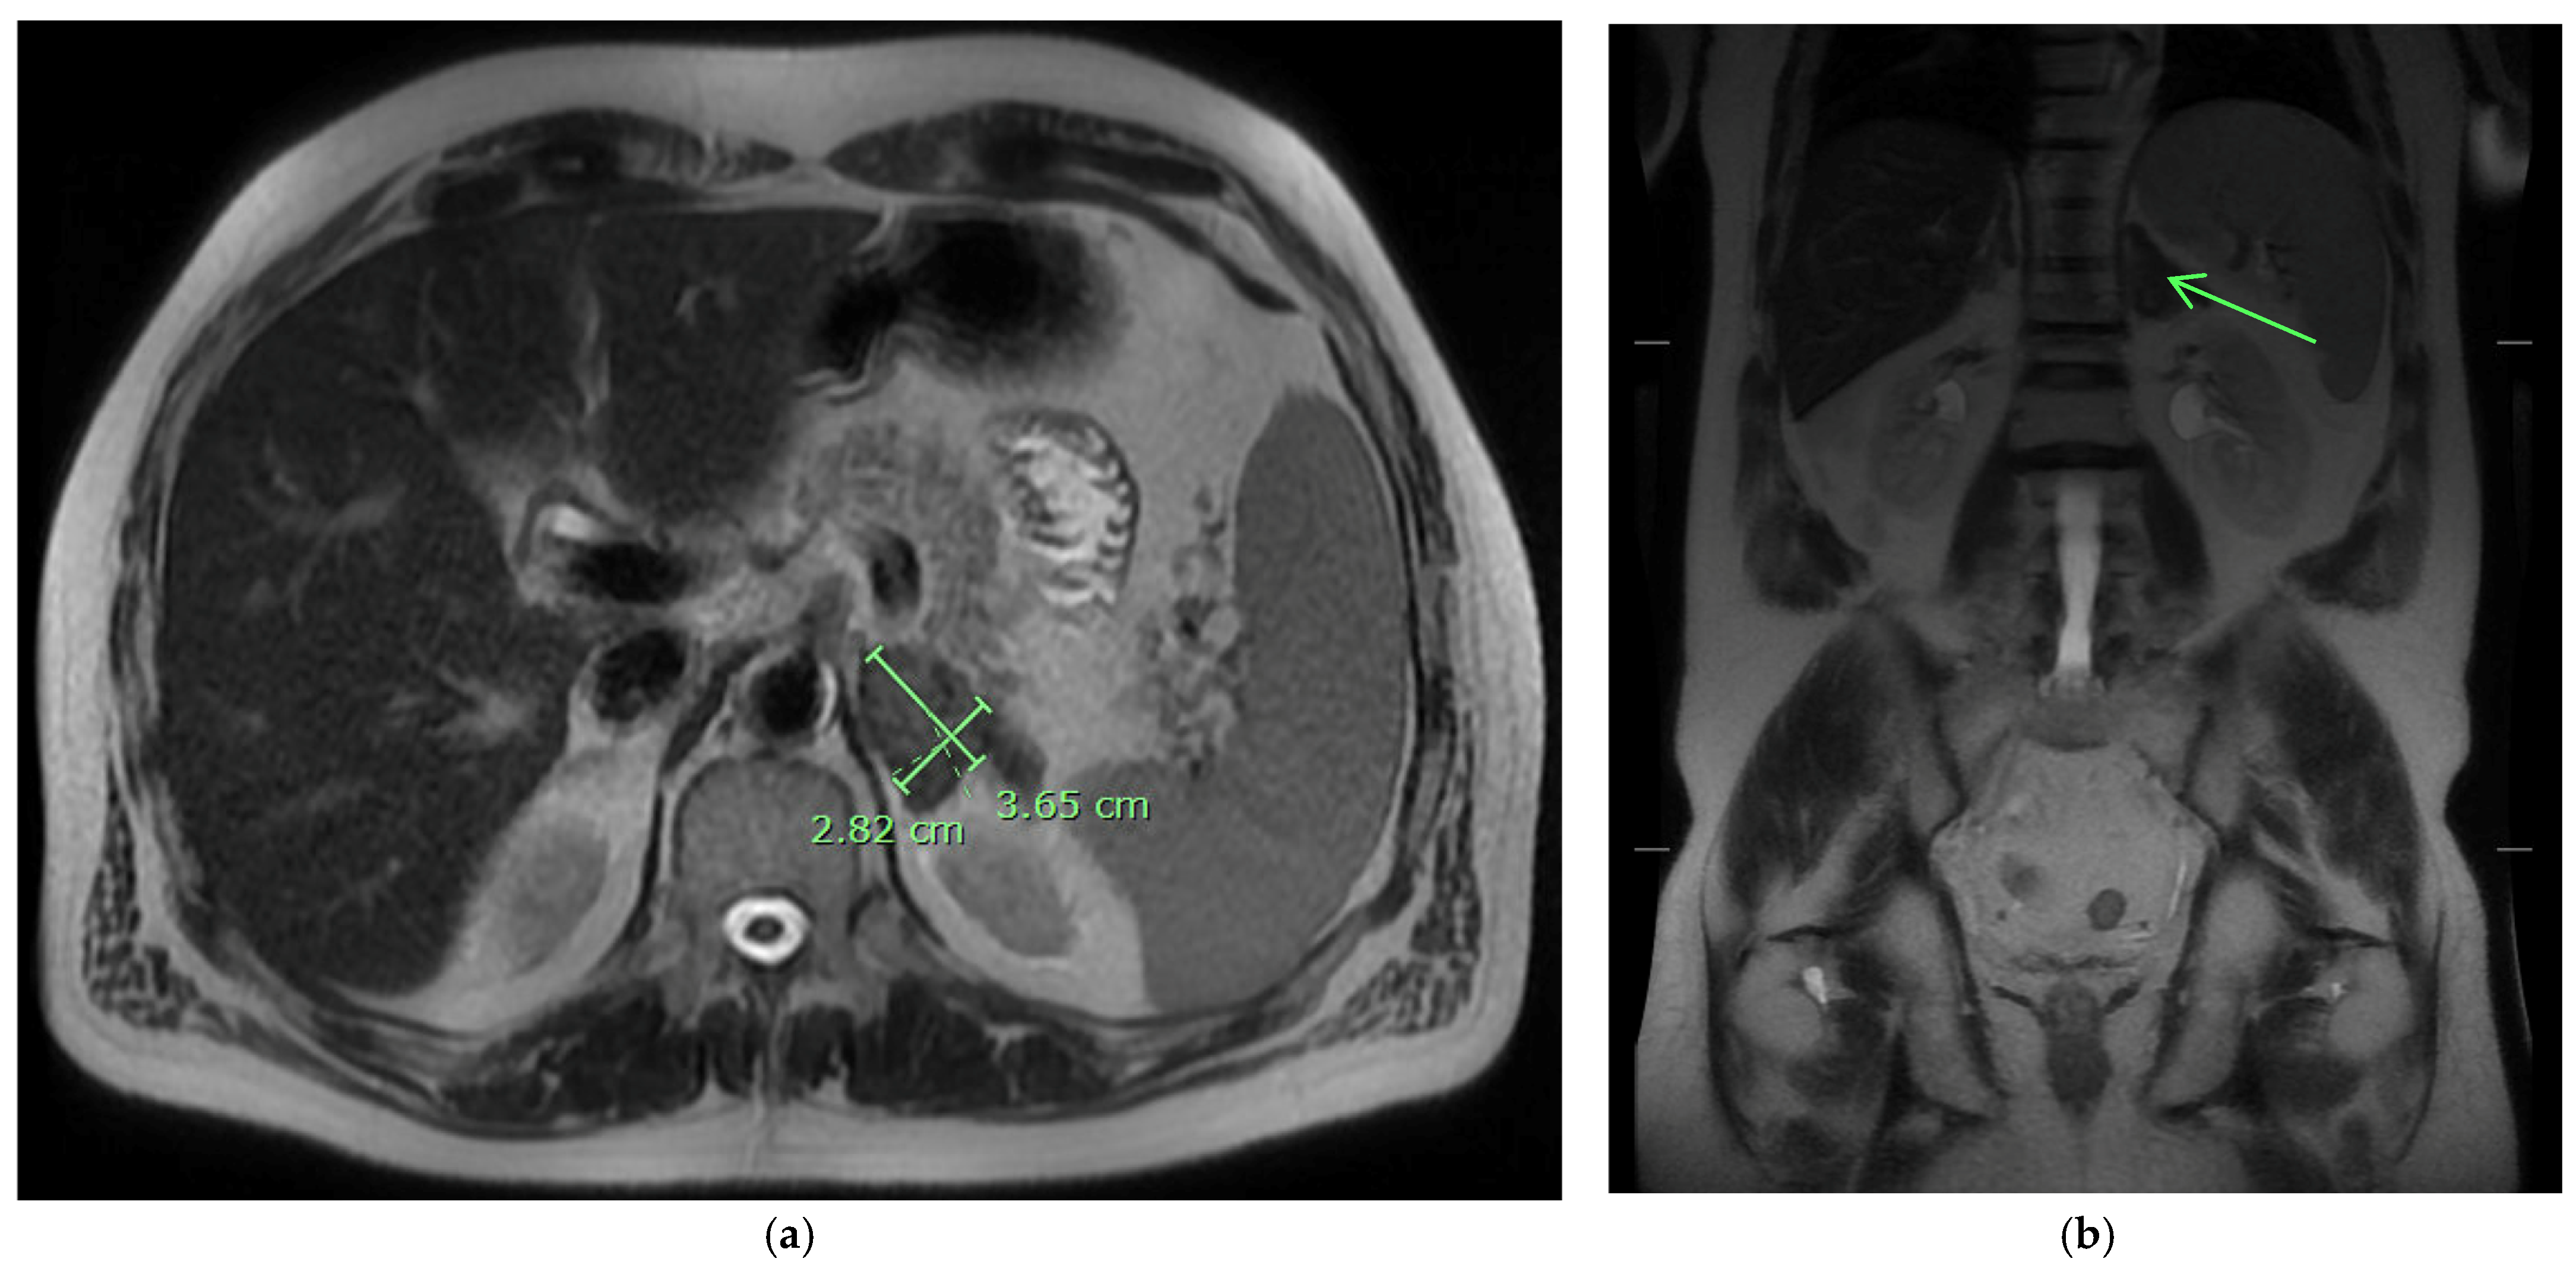

On admission, he was afebrile, saturating at 97% on room air, hypotensive with a blood pressure of 97/75, and tachycardic at 100 beats per minute, yet responsive to fluids. The physical exam was notable for a frail-appearing male with bilateral tongue nodular lesions that the patient described as painless and appeared several weeks prior to admission, see Figure 1. Due to concerns about malignancy, Oncology was consulted. Labs were significant for pancytopenia with a leukocyte count of 2.2 K/uL (NL 4–11 K/uL), hemoglobin of 12.4 g/dL (NL 13.5–17 g/dL), and platelet count of 114 K/uL (NL 130–450 K/uL). Absolute cell count showed a neutrophil count of 1.36 K/uL L (NL 1.5–7.8 K/uL) and lymphocytes of 0.49 K/uL L (NL 0.9–3.9 K/uL L). Computerized Tomography (CT) imaging of the chest, abdomen, and pelvis with contrast was significant for a left adrenal mass measuring 3.3 cm × 6 cm, see Figure 2a, which had increased from imaging 3 months prior showing a 3.2 cm × 3.5 cm mass. Imaging from 9 months ago did not show any mass. He also had a few scattered pulmonary nodules. Further work-up included Magnetic Resonance Imaging (MRI) of the abdomen and pelvis without contrast significant for diffuse thickening of the right adrenal gland up to 1 cm in the medial limb, the left adrenal mass of 6.6 cm × 3.8 cm, and splenomegaly, see Figure 2b. Due to adrenal masses, endocrinology saw the patient; he was found to have an elevated free normetanephrine level of 247 pg/mL (NL < 148 pg/mL) with a normal metanephrine range, not concerning for pheochromocytoma. The mildly elevated normetanephrine was thought to be physiologic since it was less than two times the upper limit of normal.

At the six-month follow-up, the patient reported significant improvement and resolution of all symptoms. Physical examination of the tongue showed resolution of the nodules and ulcerations (Figure 7). He had improvement in the repeat urine Histoplasma galactomannan antigen and falling Histoplasma yeast phase titers via CF. The Histoplasma antibody via immunodiffusion stayed negative. See Table 2 for a comparison of lab results. The patient had an abdominal MRI one year after his initial MRI, which showed improvement in the left adrenal mass from 3.3 × 6 cm to 2.8 × 3.7 cm (Figure 8). He is currently maintained on long-term itraconazole 200 mg TID.

Figure 8. (a) MRI abdomen pelvis w/out contrast showing 2.8 × 3.7 cm enhancing left adrenal mass at 1-year follow-up. (b) MRI imaging without contrast of adrenal mass demonstrates low T1 and T2 signals on the coronal MRI images at 1-year follow-up (see arrow).